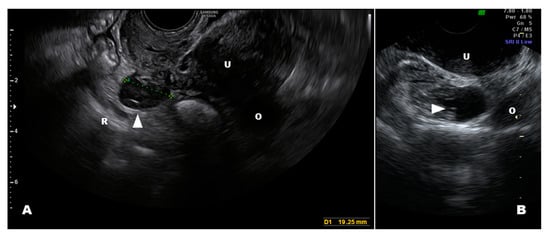

3.1. Internal Genitalia

3.2. Peritoneal and Retroperitoneal Endometriosis Lesions